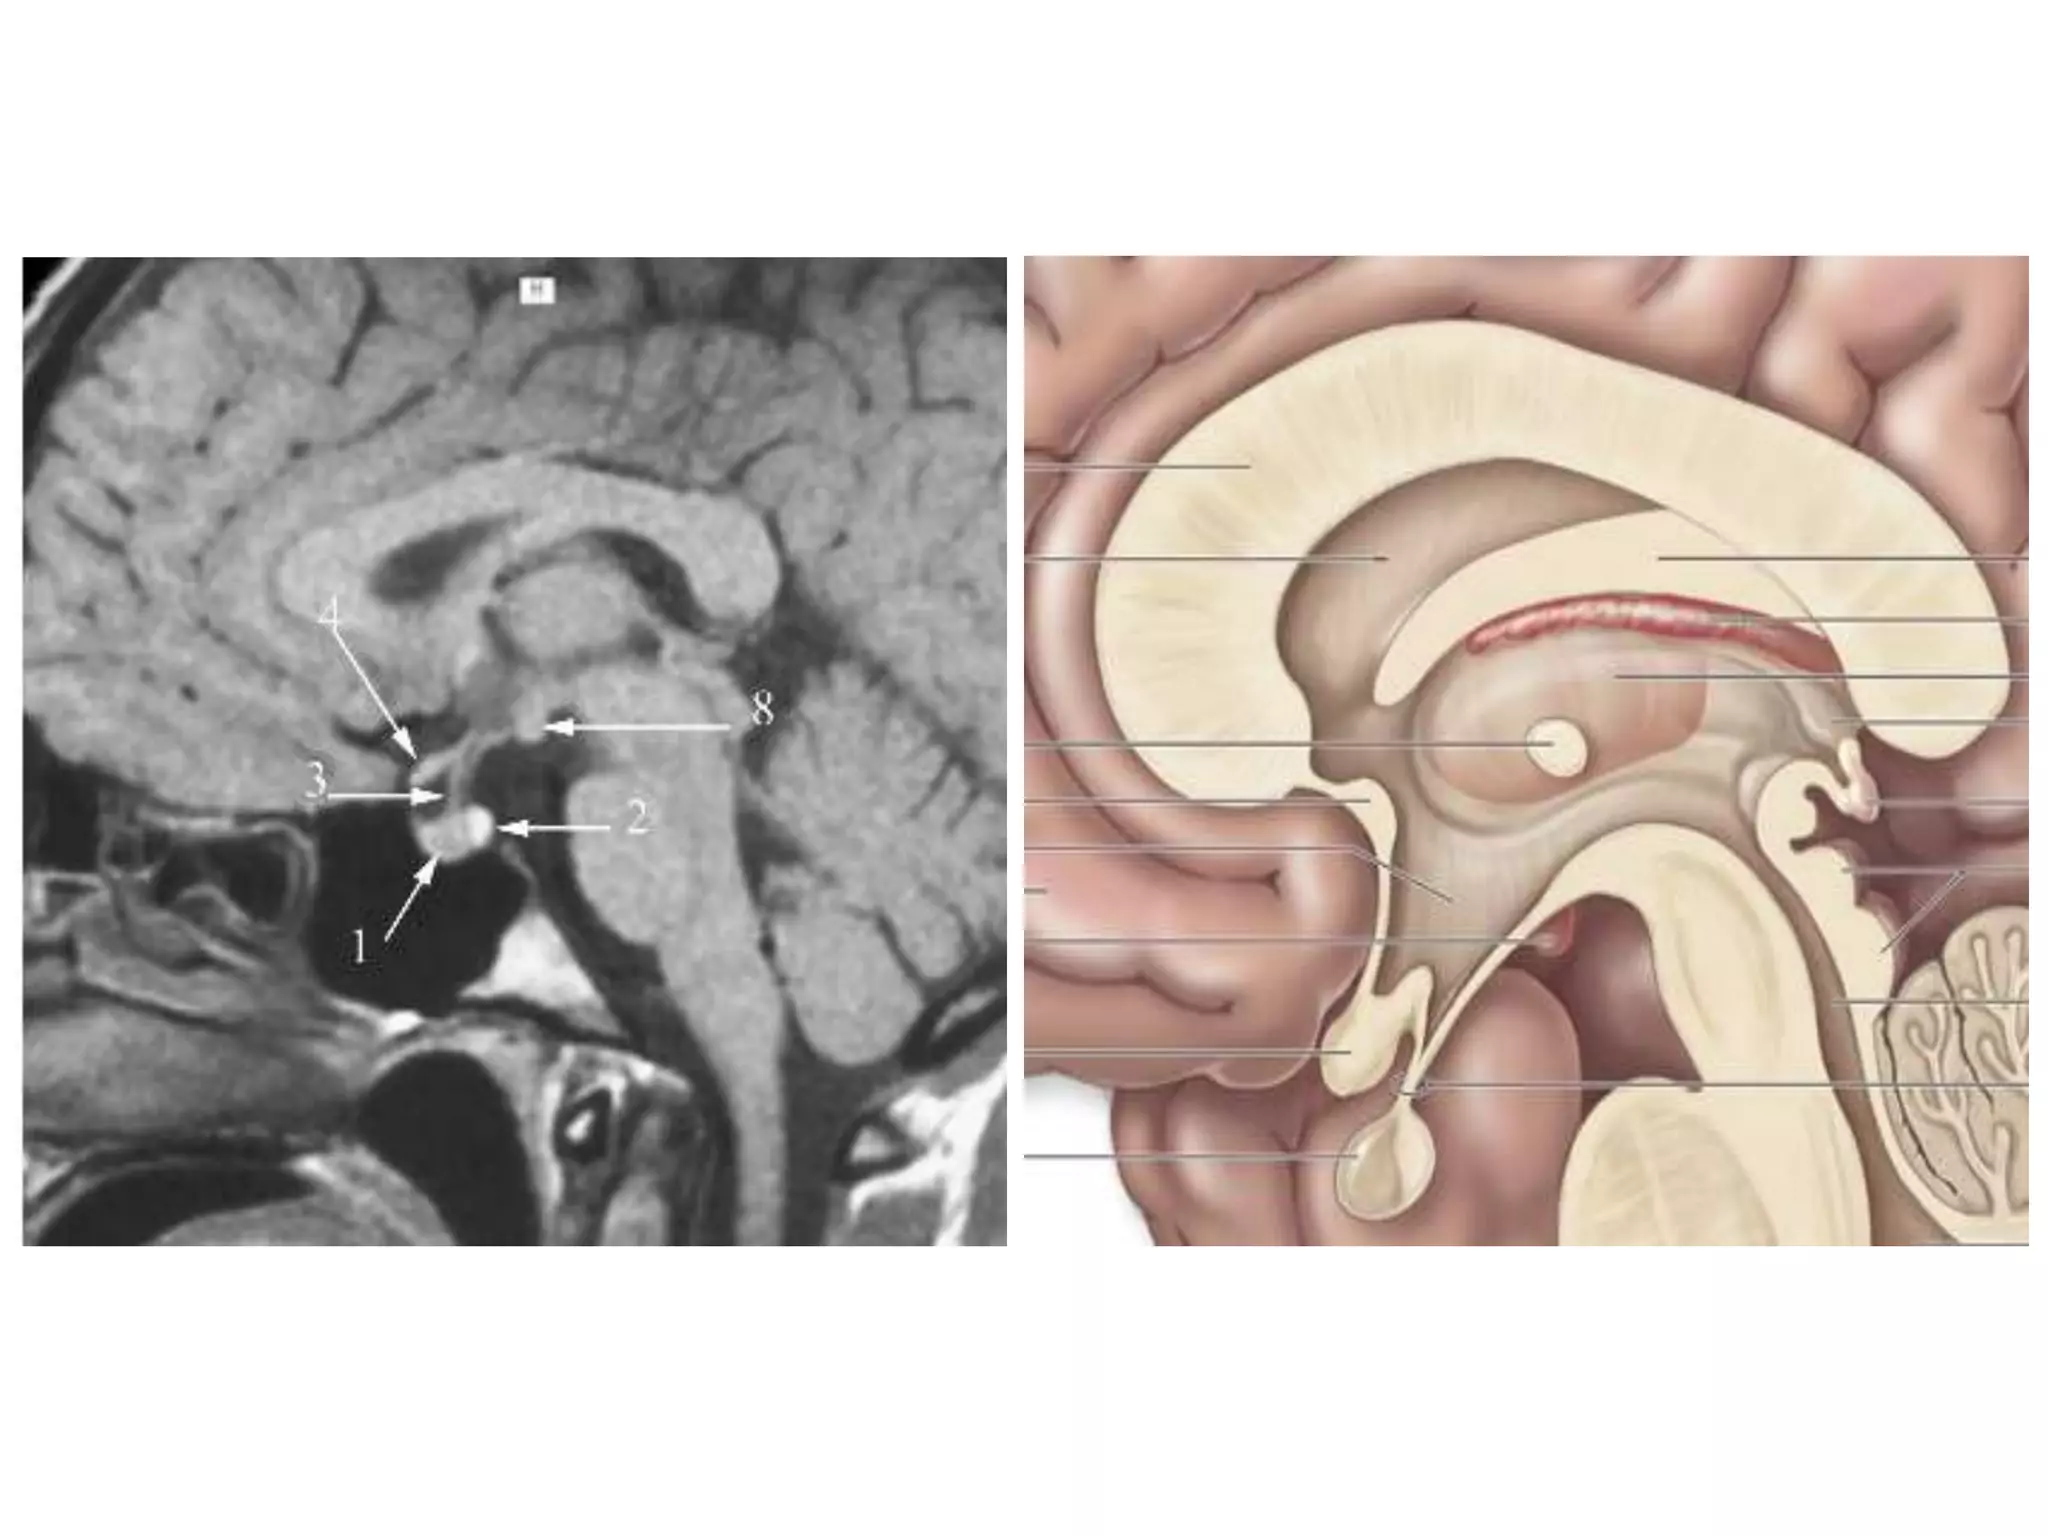

• Saggital and Coronal T1 weighted MRI – accurate

assessment of ventricles and C. callosum

• Mid Saggital section – for shape and configuration

of Aqueduct of Sylvius.

Saggital MRI : ‘C’ shaped , curving round the

thalamus.

• Radiology –

Axial MRI / CT : frontal horns separated by

S. pellucidum and posteriorly lateral ventricles diverge

and pass into temporal and occipital horns.

Coronal : frontal horns – inverted triangle

body – flattened

temporal horns – like ‘C’ on its sides.

3RD VENTRICLE

• Anterior wall – anterior commisure

lamina teminalis

• Posterior wall – suprapineal recess

pineal body with pineal recess

habenular comissure

posterior comissure

aqueduct of midbrain

• Roof - fornix                        Floor – optic chiasma

choroid plexus                        Infundibulum

tuber cinereum

• Lateral wall - thalamus                      mamillary bodies

Axial MRI / CT - narrow cleft

Saggital MRI – elongated and complex curved shape

with upward, backward & downward arc.

Aqueduct of sylvius

• Relations – antr. , Postr.

• Communications

Saggital MRI: concavity that curves downward

and forward towards the floor of 3rd ventricle.